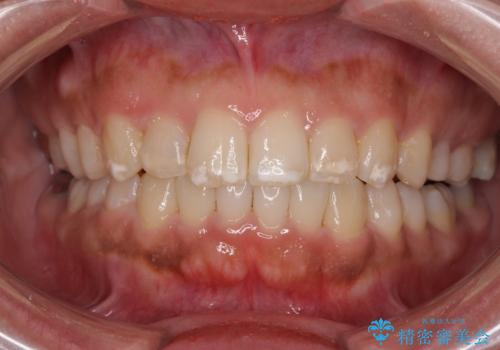

前歯のデコボコを抜歯矯正で改善 メタル装置で費用を抑える

- 前歯のデコボコと口元の突出感を気にして来院された患者様です。

非抜歯矯正ではデコボコを解消することでより口元が突出してしまうため、上下左右の小臼歯4本の抜歯を行い、ワイヤー装置による矯正治療を行うこととしました。

もう少し口元の突出感を改善したかったのですが、舌の突出癖が影響し下顎前歯が唇側に押させる仕上がりとなりました。